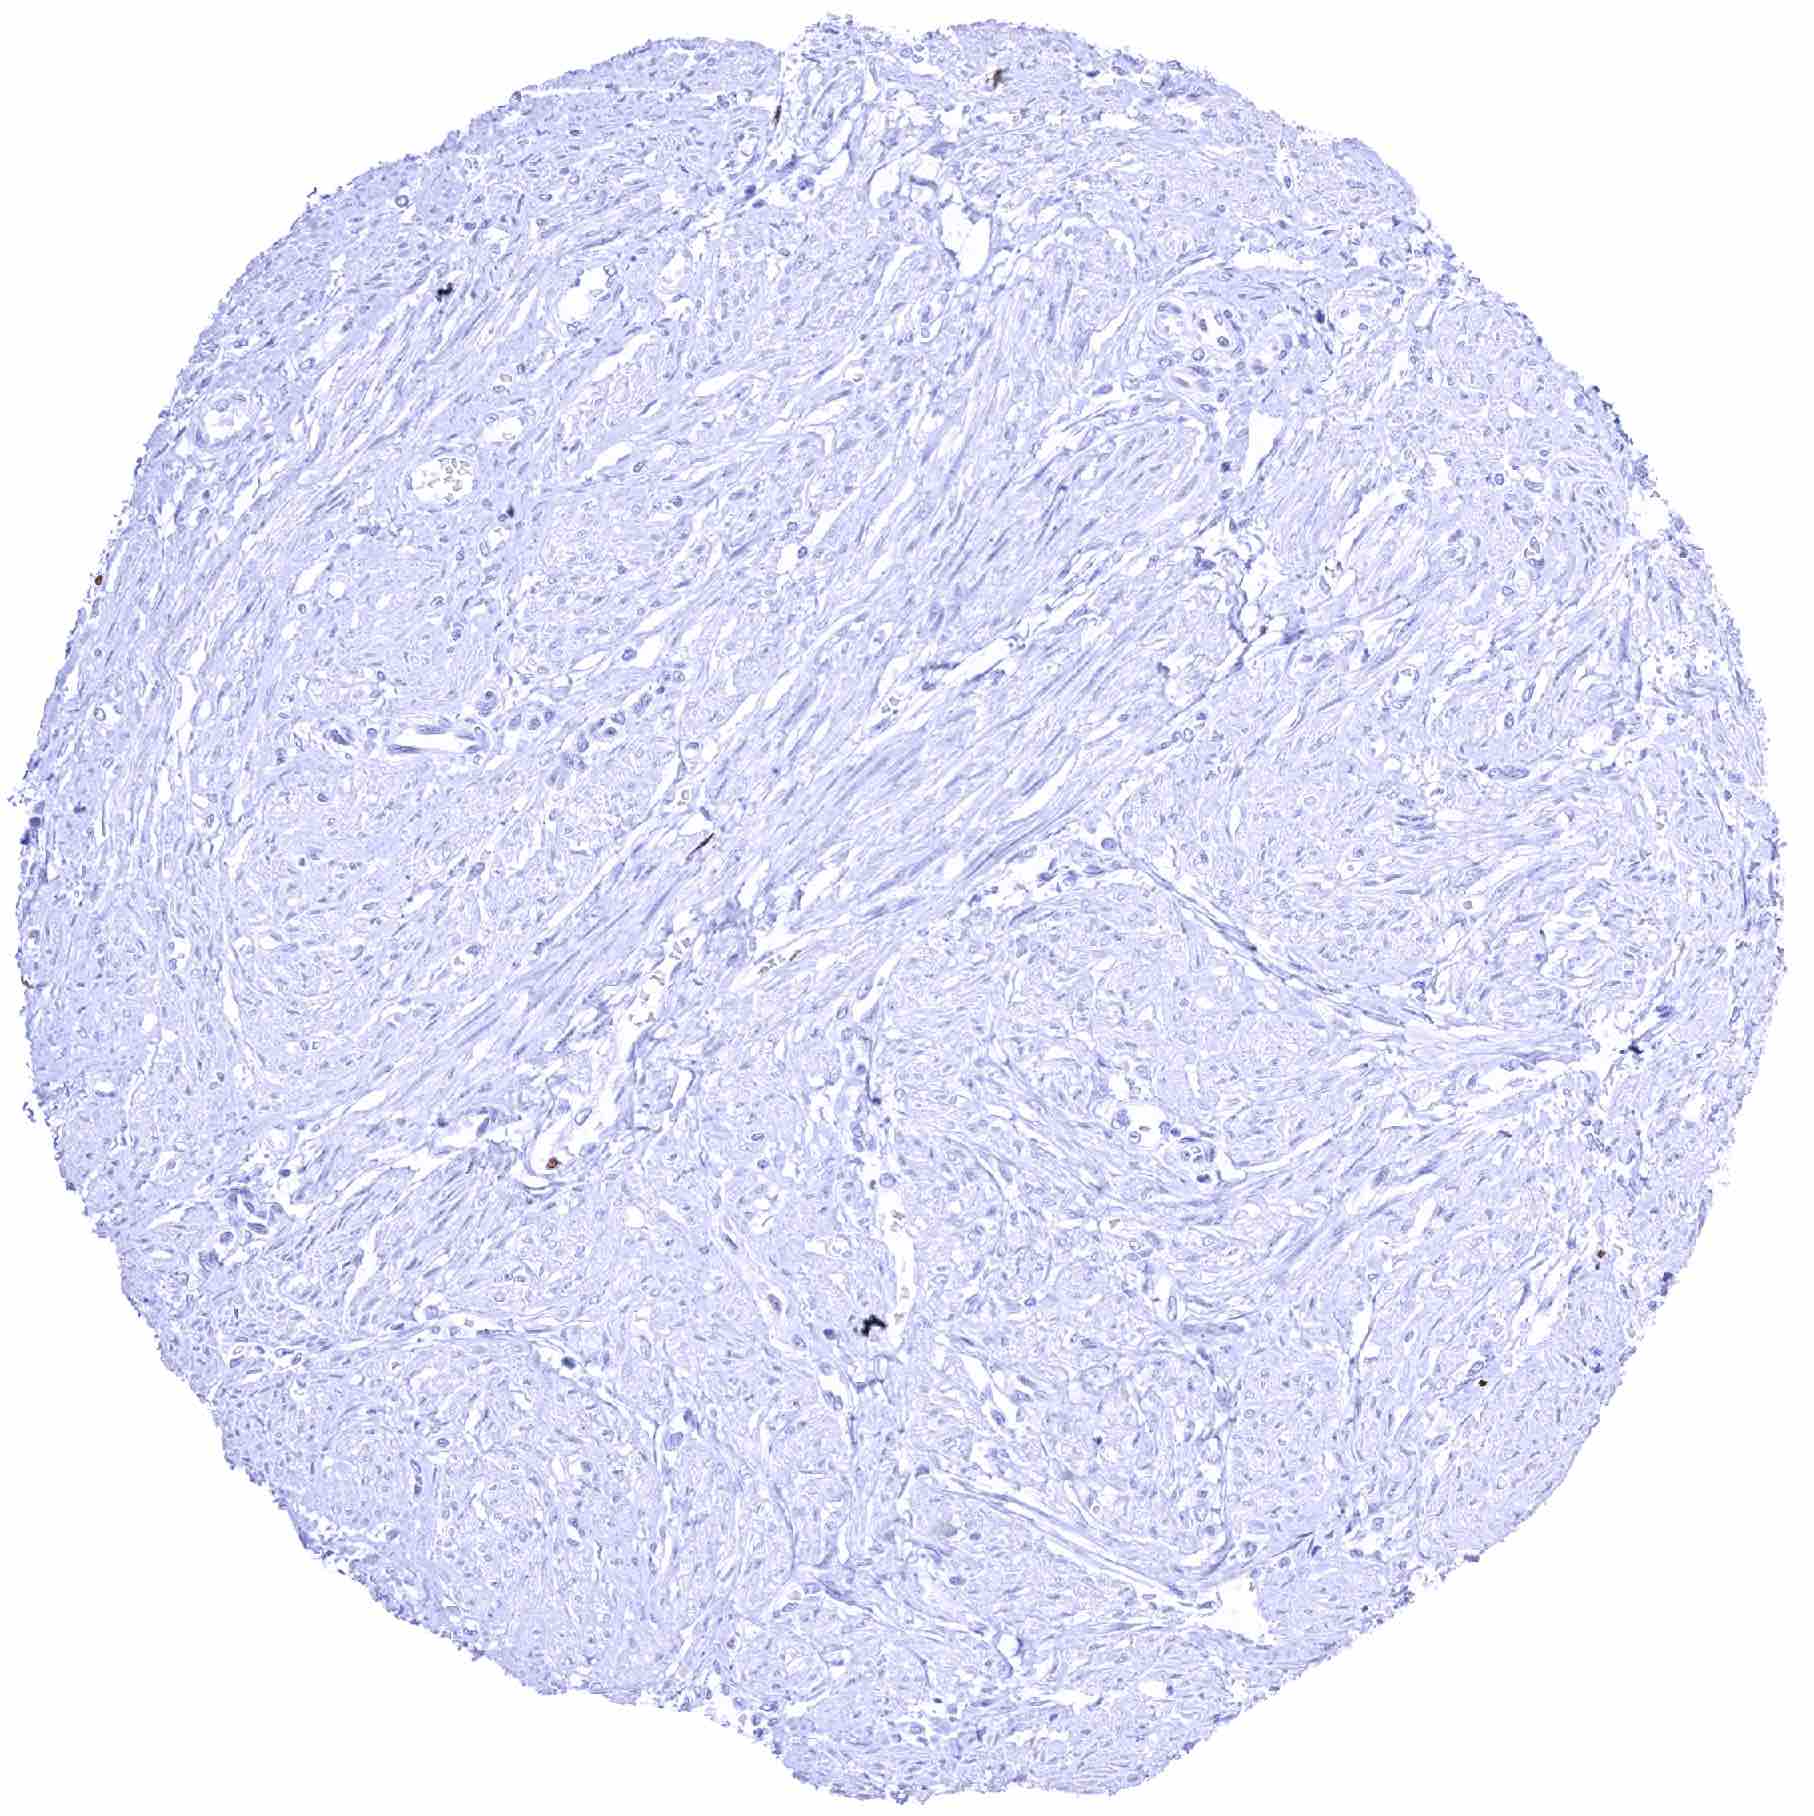

Aorta, media